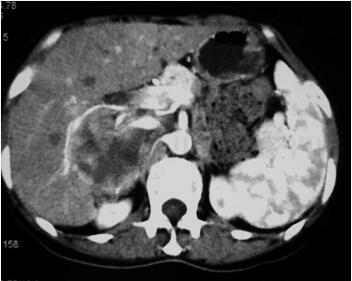

CT:右侧肾上腺区可见一巨大不均质软组织团块影,大小约6cm×6.5cm×7.2cm,增强扫描呈不均匀强化,肿块与周围组织分界欠清,右肾受压位置下移,下腔静脉受侵,其内密度不均,血管成像显示肠系膜上动脉中断,远端见狭窄后扩张,肝动脉未

见异常,双肾动脉未见明显狭窄。腹膜后未见明显肿大淋巴结,提示:右侧肾上腺占位,考虑恶性,下腔静脉及肠系膜上动脉侵犯(图49-2)。

图49-2 CT:右侧肾上腺区可见一巨大不均质软组织团块影